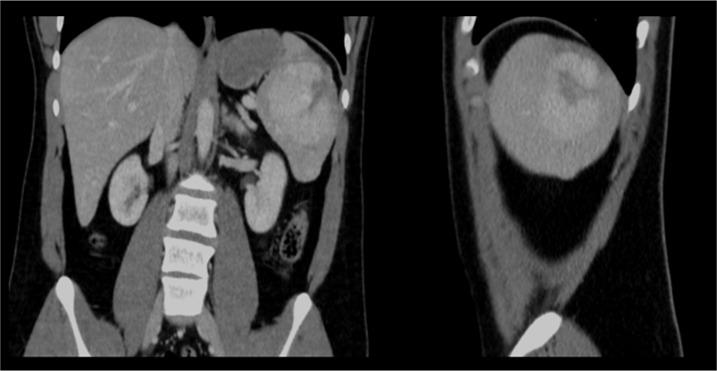

BACKGROUND Splenic hamartoma (SH) is a benign vascular lesion, usually found incidentally on abdominal images or at autopsy. Only around 200 cases have been reported since 1861, when SH was first described by Rokitansky. Although it is very rare, it is important to be familiar with it, as it may be a diagnostic challenge to distinguish SH from other mass lesions of the spleen based solely on preoperative investigations. CASE REPORT We describe a case of symptomatic, isolated, single splenic hamartoma in a 19-year-old, otherwise healthy young man who presented with upper abdominal pain, nausea, and vomiting for a few months. The examination was unremarkable. The patient has been previously evaluated with abdominal ultrasonography, which found a suspicious splenic hyperechoic lesion. Computed tomography revealed a heterogeneous 5×7 cm enhancing lesion in the spleen, concerning for splenic hamartoma. The patient underwent laparoscopic splenectomy and recovered well. The histopathology examination confirmed the diagnosis of splenic hamartoma. CONCLUSIONS Splenic hamartoma is a rare benign vascular lesion of debated etiology. Most cases are asymptomatic and are found incidentally on images, in splenectomies performed for other reasons, or at autopsy. Radiologic findings may suggest the diagnosis and new modalities have shown accuracy in distinguishing splenic hamartomas. However, resection with formal or partial splenectomy is usually still needed since the differential diagnosis is wide, from benign to aggressive lesions, and histopathology remains the criterion standard for diagnosis. Given its benign nature, we found no cases of recurrence or metastasis in the literature.